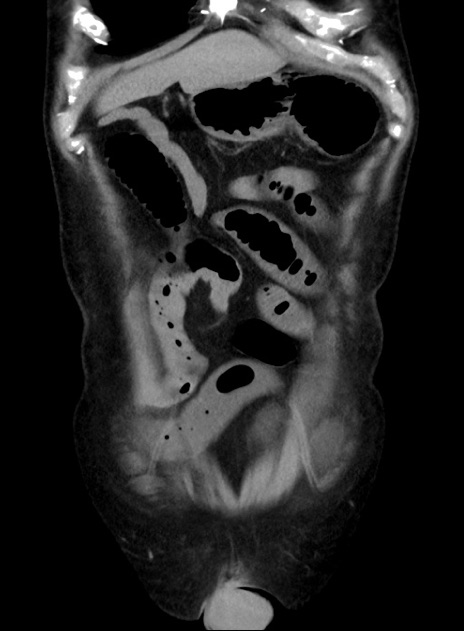

症例38(冠状断像)

【症例】70歳代 男性

【主訴】腹痛・嘔吐

【現病歴】昨晩より、嘔吐・腹痛あり。今朝になっても嘔吐あり。来院。

【既往歴】心臓バイパス手術、開腹胆摘、腸閉塞

【身体所見】BP 107/71mmHg、HR 116/min、腹部:平坦、軟、下腹部に軽度圧痛あり。反跳痛なし。

【データ】WBC 15100、CRP 0.32